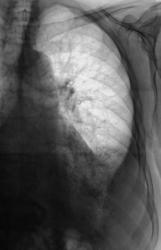

Левосторонний экссудативный плеврит.

До и после пункции.